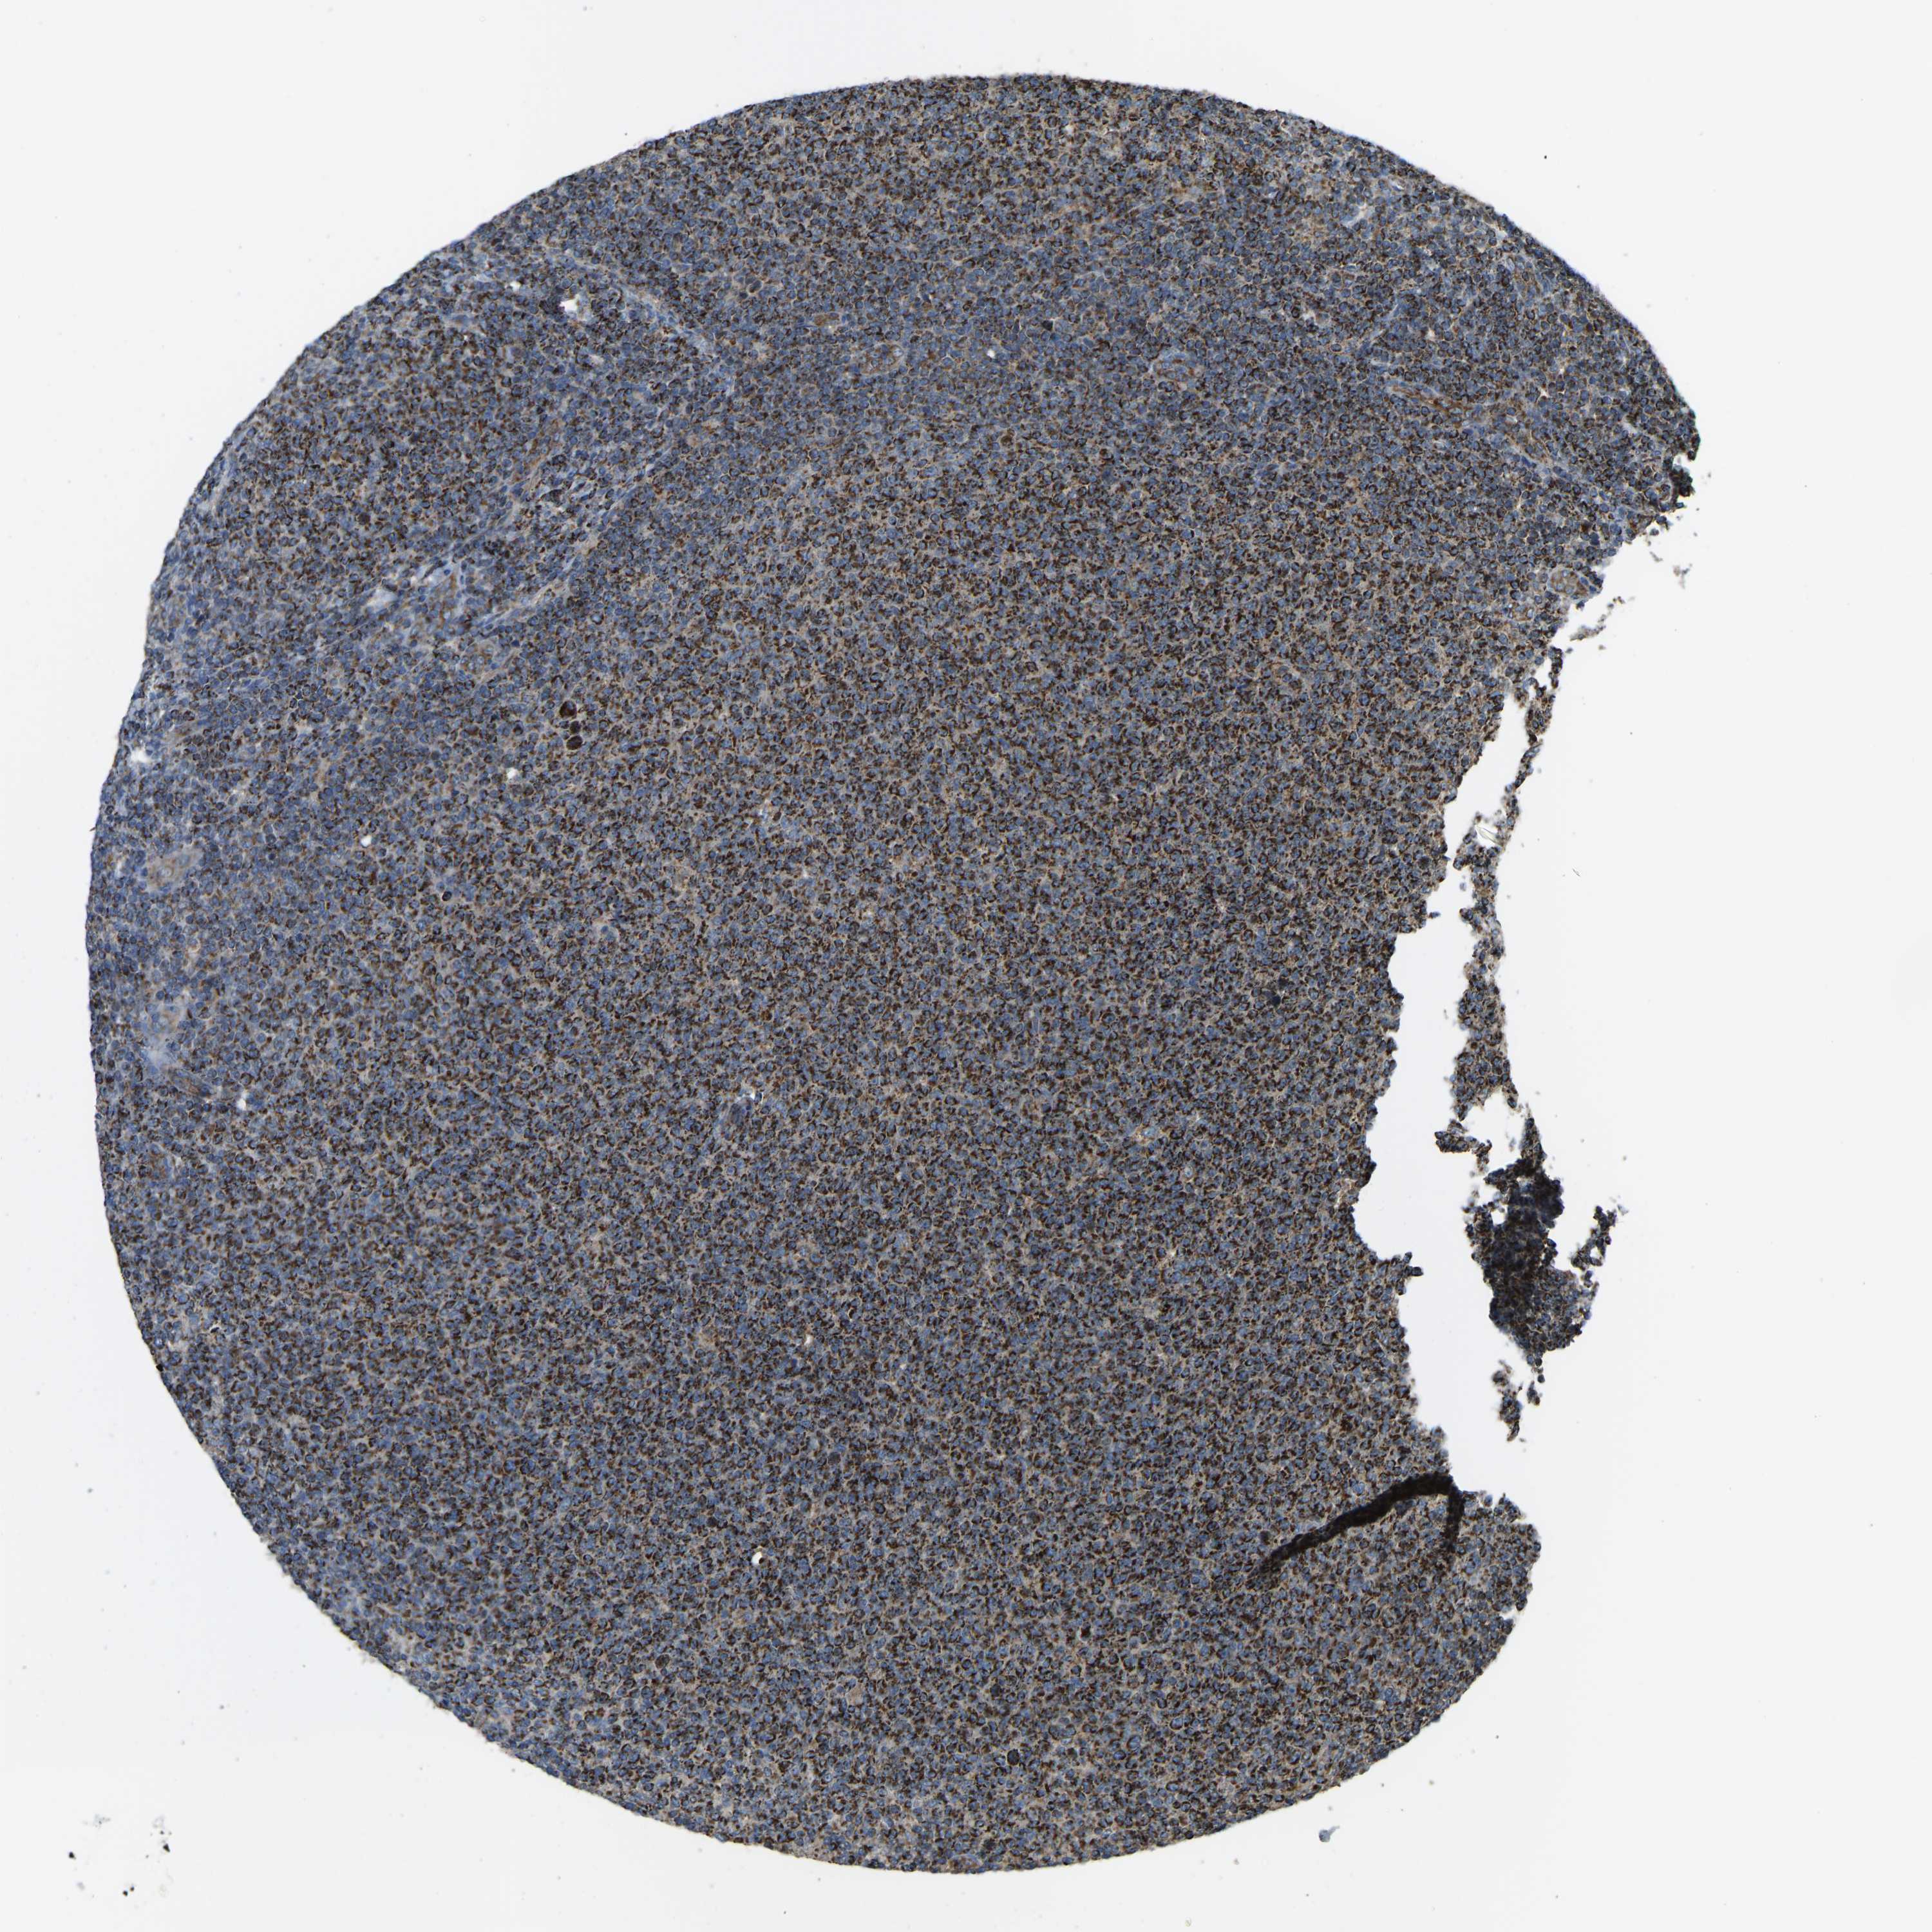

LYMPHOMA - Protein expressioni

A mouse-over function shows sample information and annotation data. Click on an image to view it in a full screen mode. Samples can be filtered based on level of antibody staining by selecting one or several of the following categories: high, medium, low and not detected. The assay and annotation is described here.

Antibody stainingi

Antibody staining in the annotated cell types in the current human tissue is reported as not detected, low, medium, or high, based on conventional immunohistochemistry profiling in selected tissues. This score is based on the combination of the staining intensity and fraction of stained cells.

Each image is clickable and will lead to virtual microscopy that enables deeper exploration of all samples and also displays staining intensity scores, fraction scores and subcellular localization as well as patient and tissue information for each sample.

Antibody HPA056069

Staining

High

Medium

Low

Not detected

Intensity

Strong

Moderate

Weak

Negative

Quantity

>75%

75%-25%

<25%

None

Location

Nuclear

Cytoplasmic/membranous

Cytoplasmic/membranous,nuclear

Malignant lymphoma, non-Hodgkin's type, High grade